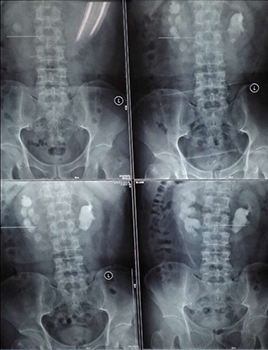

兩位患者均因腰背部疼痛來我院看診,住院后行CT等檢查確診為馬蹄腎合并腎結(jié)石,一例左腎結(jié)石大小約2.5cm,另一例右腎結(jié)石大小約3.0cm。

經(jīng)皮腎鏡取石術(shù)是泌尿外科風(fēng)險最大、技術(shù)要求最高的手術(shù)之一,而馬蹄腎是一種先天性畸形,本該相對獨(dú)立的左右兩腎的上端或者下端長在一起,形似“U”形馬蹄,且腎旋轉(zhuǎn)不良,腎盞位于腎前方,輸尿管走形異常,所以馬蹄腎患者更易出現(xiàn)各種合并癥,例如泌尿系統(tǒng)結(jié)石、感染、腎積水、尿路梗阻等。這種腎畸形增加了經(jīng)皮腎鏡取石手術(shù)的定位穿刺和建立操作通道的難度,術(shù)中出血風(fēng)險也更高。如果通道建立不理想,可能找不到結(jié)石,無法完成碎石取石。

馬蹄腎